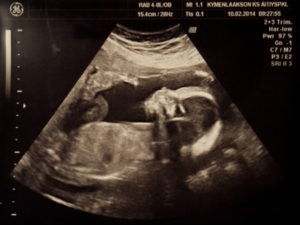

УЗИ, проведенное на 21 неделе беременности, позволяет определить пол будущего малыша, увидеть внутренние органы.

Специалист ультразвуковой диагностики оценит вероятность развития патологий, определит частоту биения сердца ребенка и состояние амниотической жидкости, установит степень двигательной активности, проведет измерения матки и плода.

При желании будущая мама сможет сама все увидеть, если УЗИ проведут в 3Д или 4Д формате, и сделать первую фотографию ребенка.

Ультразвуковое исследование на 21-й неделе беременности позволяет детально осмотреть плод, оценить его развитие, определить пол, а также проверить обвитие пуповиной, состояние плаценты, уровень околоплодных вод и матки. Кровоток в сосудах матки и плаценты анализируется с помощью допплерографии. Процедура безопасна, безболезненна и важна для специалистов.

На 21-й неделе беременности при ультразвуковом исследовании пол ребенка становится ясным. У девочек половые органы представлены двумя параллельными линиями, у мальчиков — небольшим копьевидным выступом.

На 21-й неделе беременности органы и системы плода сформированы, постепенно увеличиваются в размерах, начинают выполнять свою функцию. Головной мозг функционирует активнее – малыш улыбается, хмурится, совершает хватательные движения ручками, перебирает ножками.

На УЗИ 21-й недели беременности смотрится предлежание плода – это расположение малыша в матке:

- головное – головка ребенка направлена вниз, это физиологично;

- тазовое – головка направлена кверху, решается вопрос о виде родоразрешения.

Предлежание (локализация плода в матке) может быть тазовым, когда к входу в малый таз мамы направлены ноги, или головным (лицевым, затылочным, лобным, соответственно). Правильным является второе.

Но, на 21 неделе беременности положения малыша еще не является окончательным. В силу своей подвижности, он может перевернуться еще не один раз.